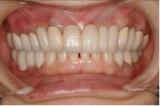

審美歯科治療 | ||

| 見た目の美しさだけにとらわれてはいけません。機能性を十分に満たした美しさが本当の審美歯科です。またそれが永続性のあるものでなければ意味がありません。歯グキの色素を除去し綺麗なピンク色にし、下の前歯を漂白し(両方とも殆ど痛みはありません)上の前歯にセラミック冠を被せました。 |

【治療前】 |

【治療後】 |